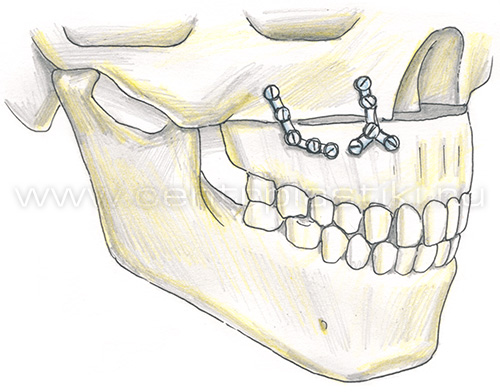

Остеотомия верхней челюстиПоказания Коррекция аномалий развития верхней челюсти (микрогнатия, ретрогнатия верхней челюсти). Остеотомию на верхней челюсти проводят как этап ортодонтического лечения. Операция Остеотомия верхней челюсти выполняется внутриротовым доступом под эндотрахеальным наркозом, выполняется разрез слизистой оболочки полости рта и надкостницы, разрез производят несколько выше переходной складки верхней челюсти от 7 до 7 зубов. Края раны раздвигаются, тем самым осуществляется доступ к передней стенке верхней челюсти.  На передних и боковых стенках верхней челюсти слева и справа производятся разметки линий распилов.  Специальными пилками проводится остеотомия по разметкам.  Затем отделяется распиленный фрагмент и перемещается в заранее выбранное положение.   Фиксация перемещенного фрагмента в новом положении осуществляется титановыми мини-пластинками.  Длительность Операция занимает от 1,5 до 3 часов и проводится под наркозом. В течение 1 месяца после лечения сохраняется отечность мягких тканей лица, может отмечаться нарушение чувствительности верхней губы и щек, чувствительность восстанавливается самопроизвольно через некоторое время. В ряде случаев после операции для обеспечения хорошего срастания костей проводят межчелюстное шинирование , верхняя и нижняя челюсти фиксируются друг к другу специальными приспособлениями, так что полное открытие рта невозможно. В этот период (2-3 недели) возможно питание только протертой и жидкой пищей. После операции остеотомии верхней челюстиВ послеоперационном периоде возможно ношение ортодонтической брекет системы для правильного смыкания зубных рядов верхней и нижней челюстей. Реабилитационный период В течение 1-3 суток после операции рекомендовано нахождение в стационаре под наблюдением медицинского персонала (длительность нахождения в стационаре может быть продлена до 10 суток в зависимости от течения послеоперационного периода). Длительность реабилитационного периода зависит от восстановительных способностей организма. Эффективность Окончательный результат операции можно наблюдать через 3-6 месяцев. В послеоперационном периоде могут сохраняться отеки в течение 2-4 недель, в зависимости от индивидуальных особенностей восстановление протекает с разной скоростью. |